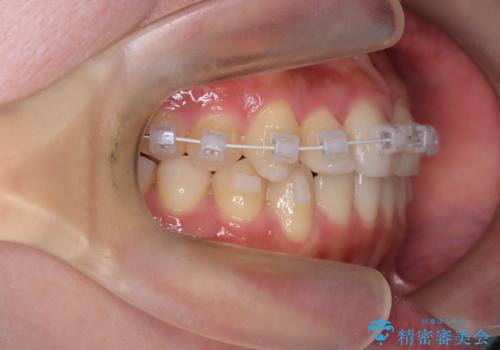

- 矯正装置

- 審美装置

インビザラインを希望されておりましたが、20時間もつけることができなかったためワイヤー矯正にて叢生の改善を行っています。

右上の側切歯(前から2番目の歯)が90度程度ねじれている状態でしたが、1月に1回のワイヤー交換できれいに並ぶことができ満足いただけました。

捻れた歯の治療に関しては、ワイヤー矯正の方が仕上がりがきれいに治りやすいです。